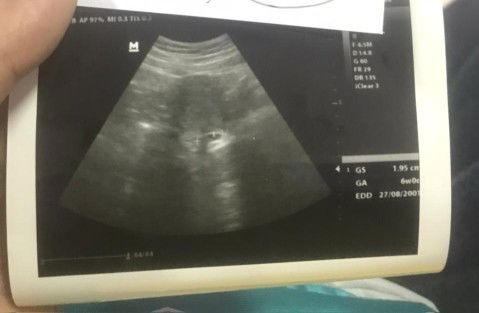

Assalamualaikum wr wb,Hallo bun, aku di apk ini sudah masuk hamil 7minggu bun, tp pas usg kata dokter spognya aku baru 6 minggu dan ukuran kantong masih 1.95cm bun, normal ngga yah bun? Soalnya waktu hamil 5 minggu (usg pertama)kata bidan waktu usg di bidan juga baru ada kantong ##seriusnanya #bantusharing #ingintahu #firstmom